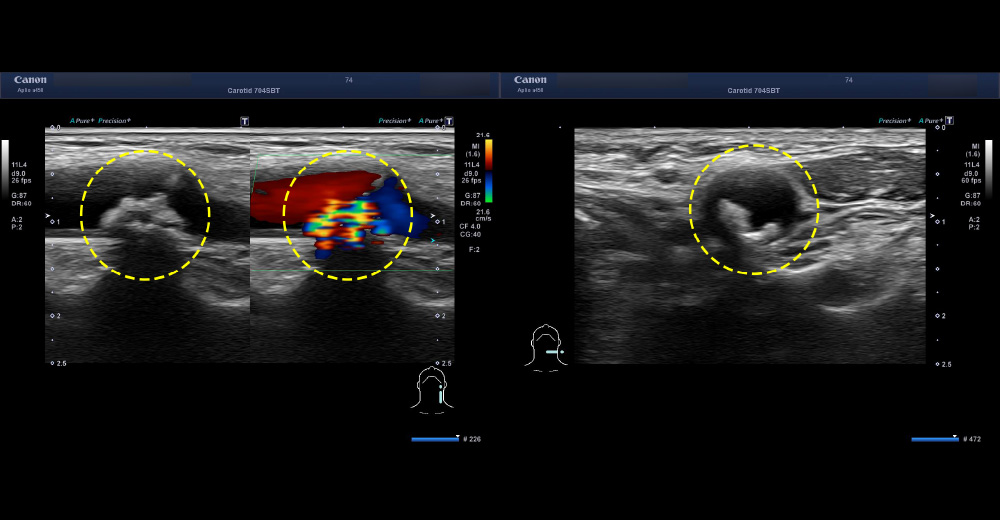

1. 頸動脈血管エコー

中期 頸動脈エコー 頸動脈狭窄症例